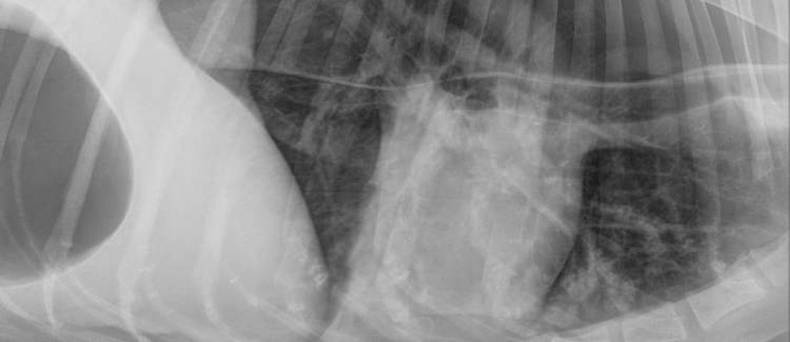

Een ontsteking van de anaalklieren of de anaalzakken is een vaak voorkomend probleem bij de hond. Honden hebben aan de linkerkant en de rechterkant van  anus een anaalzak met klieren die een vloeistof afscheid die stinkt. Dit is een geur-merker en deze heeft een functie met betrekking tot de sociale omgang van de hond.

De uitgang van het anaalzakje is zeer klein en raakt makkelijk verstopt. Dan zullen de klieren vocht blijven maken en dit kan dan niet weg, met overvulling tot gevolg. Er treedt dan makkelijk een ontsteking op. Er zijn bepaalde honden die hier erg vatbaar voor zijn.

Als de anaalzakken te vol zijn, zal de dierenarts ze leeg gaan drukken. De vloeistof komt naar buiten en de nauwe doorgang wordt weer open gemaakt. Bij een infectie is antibiotica nodig. Een abces zal opengesneden worden. Als anaalklierontstekingen steeds terugkomen kan overwogen worden de anaalzakken weg te halen.